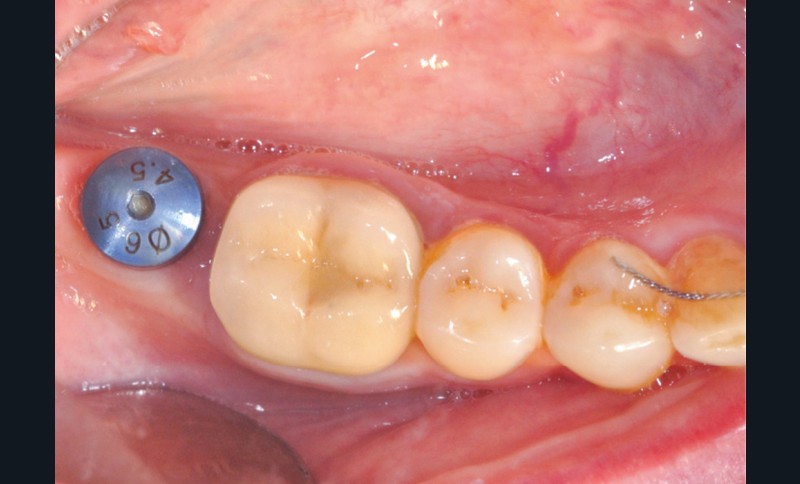

Les études montrent que si le puits est proche du centre, en ménageant 2 mm au moins de céramique autour, le risque de fracture est faible. D’où l’intérêt d’un excellent positionnement implantaire (fig. 6).

Ainsi, une dent présentant une très petite face occlusale ou palatine/linguale peut indiquer une prothèse scellée pour des raisons mécaniques (voir fig. 9 page suivante).

Un axe trop divergent, même après système de correction d’axe, peut imposer la réalisation d’une coiffe scellée pour éviter un puits de vis sur un bord libre, par exemple (voir fig. 10, page suivante).